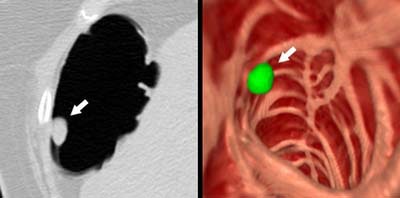

![]() |

| Above, soft-tissue filling defect in the lateral rectum. Straight line in the axial CT image at left represent CAD detection. Arrow in image at right indicates the same defect in the coronal view. From Fletcher JG, Summers RM, Johnson CD, MacCarty RL, Wilson LA. Lessons in Detection: Contribution of Computer-aided Detection with Perceptively Challenging Lesions at CT Colonography. Supplement to Radiology November 2002, Vol. 225, p. 304. RSNA December 1-6, 2002, Chicago. Image courtesy of Dr. Joel Fletcher, © Mayo Medical Foundation, 2002. |